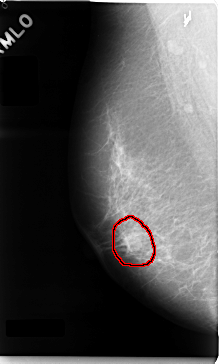

C_0035_1.RIGHT_MLO

RIGHT_MLO LINES 4720 PIXELS_PER_LINE 2856 BITS_PER_PIXEL 12 RESOLUTION 50 OVERLAY

FILE: C_0035_1.RIGHT_MLO.OVERLAY

TOTAL_ABNORMALITIES 1

ABNORMALITY 1

LESION_TYPE MASS SHAPE OVAL MARGINS MICROLOBULATED

ASSESSMENT 5

SUBTLETY 5

PATHOLOGY MALIGNANT

TOTAL_OUTLINES 1

BOUNDARY